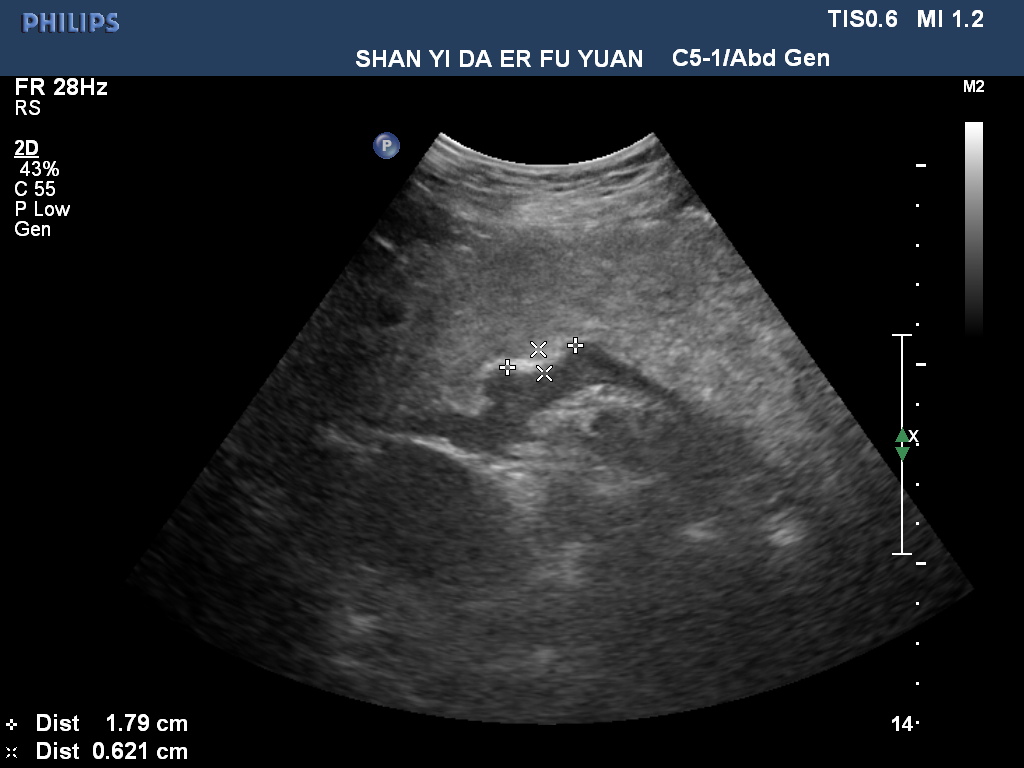

胃內(nèi)異物—磁力珠